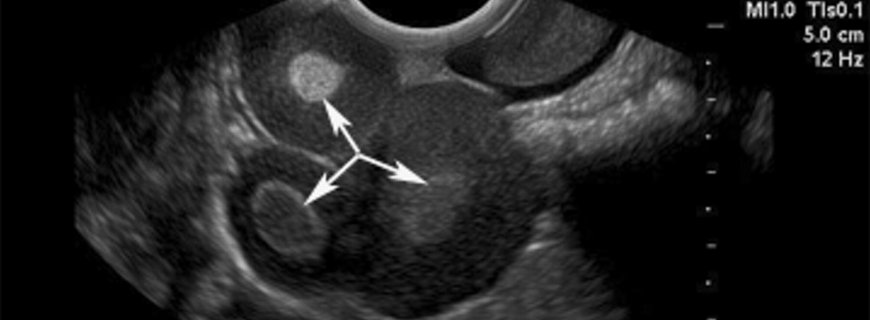

Yumurtalık kanserinin başlangıcı sinsidir, tanı esnasında yumurtalıklara sınırlı hastalık varlığı yalnızca %25 olgudadır. Belli belirsiz olmakla birlikte karında rahatsızlık ve şişkinlik, hazımsızlık, çabuk doyma, bulantı, kabızlık, kasıklarda bası hissi, sık idrara çıkma, cinsel ilişkide ağrı, halsizlik ve kısa soluma görülebilecek belirtilerdir. Erken evre yumurtalık kanserlerinin büyük çoğunluğu rutin muayene esnasında belirti vermeyen bir kistin fark edilmesiyle veya başka bir sebeple radyografik inceleme yapılırken tesadüfen ile tanı alır. İlerlemiş hastalık genellikle belirgin hale gelmesi veya karın içinde aşırı sıvı birikimi ile tanı alır. -